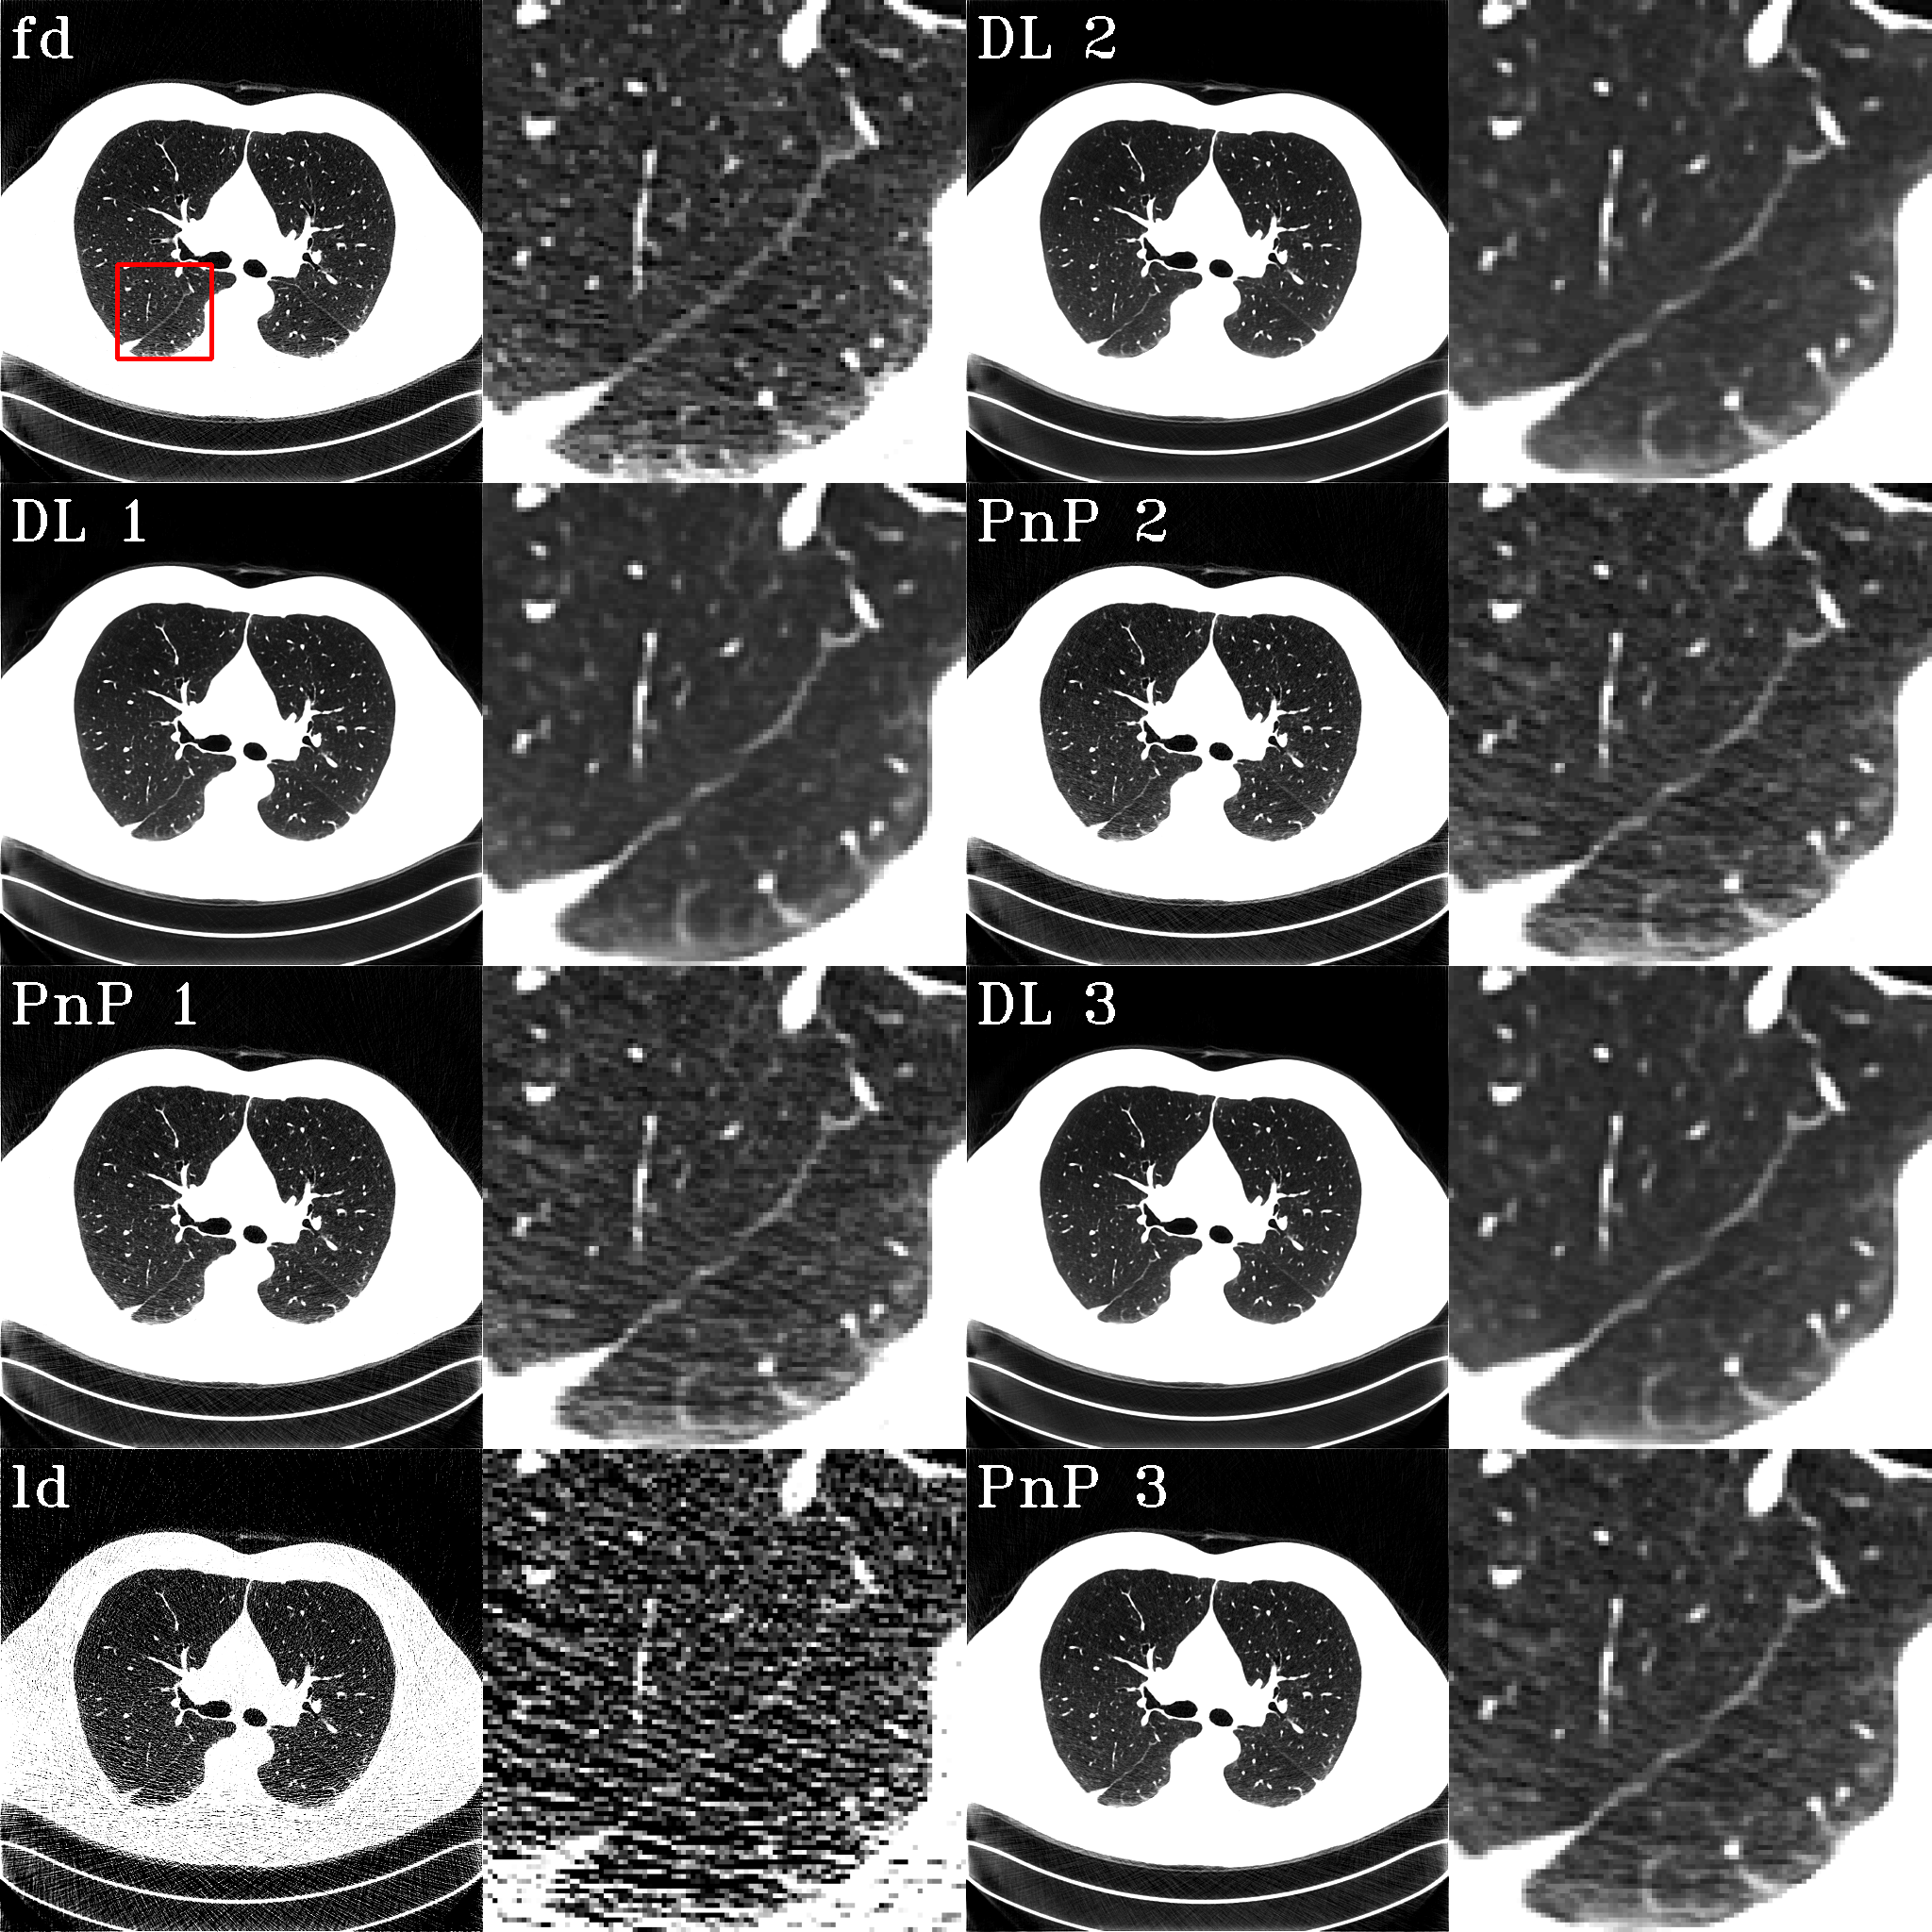

Fig. 3 shows examples of different intermediate results. The conventions in the images are the same as above. The images are shown in a window of [-1000, -267] HU to highlight the lung tissues. One observation is that, as shown in the enlarged area, the DL plugin inevitably smooths the resultant images due to distinct noise patterns of full- and low-dose images. In other words, the noise pattern of full-dose images cannot be predicted, given the noisy low-dose images as input. As a result, to minimize the loss function, the network adopts the strategy to predict a clean image that minimizes the distance expectation over all possible latent full-dose images. While the fine textures are brought back from the sinograms by the optimization process, noise independent of full-dose images is inevitably introduced, resulting in a higher Euclidean distance from the ground-truth full-dose images.

Refer to caption

Fig. 3: Example images. The red box bounds the enlarged area, which is shown to the right of each image.